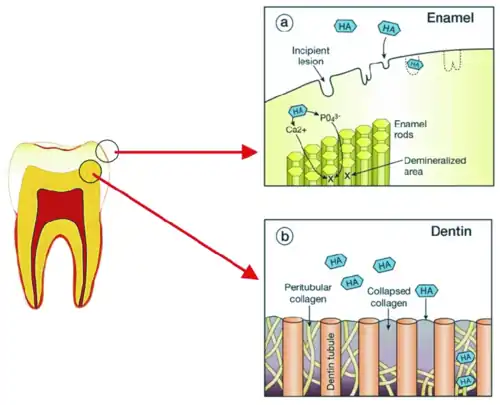

- ↑ Les bactéries cariogènes de la plaque dentaire métabolisent par fermentation les glucides alimentaires. Les déchets produits sont des acides organiques qui baissent le pH local, ce qui entraîne une dissolution acide interprismatique puis intraprismatique des cristaux d'hydroxyapatite (déminéralisation en surface de l'émail : lésion cavitaire de la figure 1), et secondairement une dissolution des cristaux de la dentine péritubulaire puis intertubulaire (figure 2). La phase de reminéralisation est un processus naturel de réparation par reprécipitation des lésions carieuses initiales, qui se déroule principalement entre les repas. Le pouvoir tampon de la salive induit une remontée du pH buccal qui conduit au dépôt des cristaux ayant été dissous, selon trois schémas distincts (restauration de cristaux partiellement dissous, formation de nouveaux cristaux ou croissance des cristaux résiduels). Cf (en) Xiaoke Li, Jinfang Wang, Andrew Joiner, Jiang Chang, « The remineralisation of enamel: a review of the literature », Journal of Dentistry, vol. 42 (Suppl. 1), , p. 12-20 (DOI 10.1016/S0300-5712(14)50003-6).